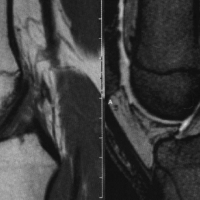

• 前交叉韧带损伤MR分级

膝部前交叉韧带撕裂